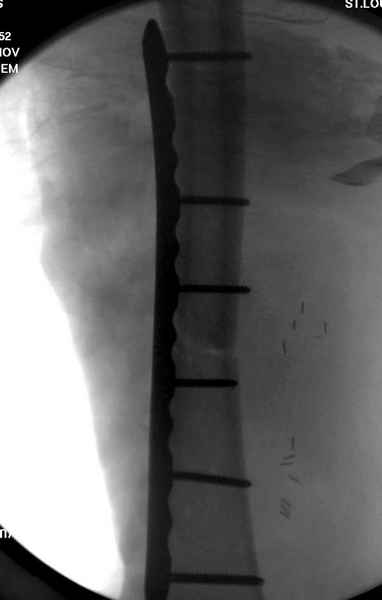

Больному с политравмой установлен наружный "spanning-bridging" фиксатор, после нескольких Irrigation&Debridment на фоне отрицательного посева из раны, через открытый участок установлен 4.5 mm Locking Plate.

На фоне фиксированного перелома бедра мероприятия по восстановлению мягкотканого покрова. Перелом голени зафиксирован после стабилизации бедра традиционным методом.

Антибиотические бусы могут быть оставлены в мягких тканях на длительный срок и не обязательно их удалять.